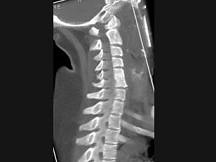

问题 男,35岁,反复颈部不适20余年,结合图像,最可能的诊断是?(?)

选项 A.颈椎椎体融合 B.颈椎结核 C.颈椎退行性变 D.颈椎压缩性骨折 E.颈椎骨转移瘤

答案 A